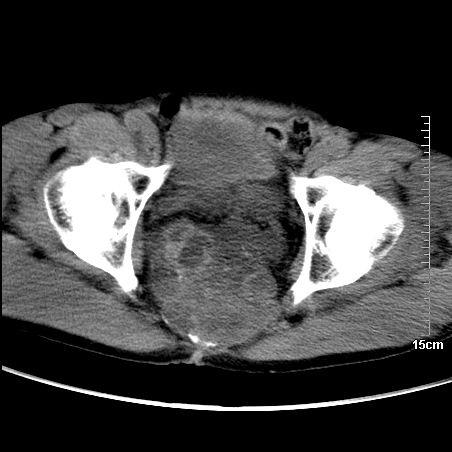

标题: CT16886:骶尾部占位:1.脊索瘤?2.巨细胞瘤?

增强:

1、骶尾部巨大软组织肿块,部分骶尾骨以被软组织肿块代替,呈不规则侵蚀;病变突向盆腔内;增强扫描病变呈不均质强化;首先考虑脊索瘤。不支持的一点就是病变内无钙化。

2、发生于骶尾椎者须与骨巨细胞瘤鉴别,骨巨细胞瘤一般发在上疗骶椎,肿瘤内无钙化,一般无侵袭性生长的表现。